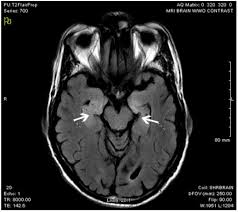

Mri findings which suggest encephalitis. We studied 5 patients with rasmussen's encephalitis, assessing clinical history and mr images. Mri findings in two cases confirmed by polymerase chain reaction. Treatment consists of making a sling by pinning the shirt sleeve of the involved side to the opposite side of the shirt. There is no particular age, sex, or seasonal predilection. Common symptoms include headaches, fevers, drowsiness, hyperactivity, and/or general weakness. Rasmussen's encephalitis is a progressive hemispheric atrophy of unknown origin. Mri findings may be very subtle or may even be negative, therefore a high index of suspicion is mandatory! Figure 1 shows common mri findings in different types of encephalitis. Herpes simplex virus (hsv) encephalitis hsv encephalitis (hsve) is the most common cause of infectious encephalitis (1); Herpes simplex encephalitis (hse) is a rare neurological disorder characterized by inflammation of the brain (encephalitis). Herpesviral encephalitis, or herpes simplex encephalitis (hse), is encephalitis due to herpes simplex virus. Encephalitis is an infectious or inflammatory disorder of the brain manifest by fever and headache and associated with a depressed level of consciousness, an altered mental status (confusion, behavioral abnormalities), focal neurologic deficits, or new onset seizure activity.

Figure 1 shows common mri findings in different types of encephalitis. Mri findings may be very subtle or may even be negative, therefore a high index of suspicion is mandatory! One potential etiology for mesial temporal sclerosis. If findings are present, they typically consist of subtle low density within the anterior and medial parts of the temporal lobe and the island of reil. Imaging findings in patients with these disorders can also be quite variable, but recognizing characteristic findings within limbic structures suggestive of autoimmune encephalitis can be a key step in alerting clinicians to the potential diagnosis and ensuring a prompt and appropriate clinical.

Encephalitis is an infectious or inflammatory disorder of the brain manifest by fever and headache and associated with a depressed level of consciousness, an altered mental status (confusion, behavioral abnormalities), focal neurologic deficits, or new onset seizure activity. Common symptoms include headaches, fevers, drowsiness, hyperactivity, and/or general weakness. Mri imaging of the brain is usually nonspecific, or even normal, but limbic encephalitis usually produces some herpes simplex virus (hsv) encephalitis is an important cause of similar presentations, and should be ruled out by csf pcr for hsv, which. Mri findings may be very subtle or may even be negative, therefore a high index of suspicion is mandatory! Hse has a bimodal distribution, commonly affecting patients younger than 20. In the case of lg1 encephalitis, hyperintensities in the basal ganglia are common ( 22 ). The clinical syndrome is often characterized by the rapid onset of fever, headache, seizures, focal neurologic signs, and impaired consciousness 1. Herpes simplex virus (hsv) encephalitis hsv encephalitis (hsve) is the most common cause of infectious encephalitis (1); Magnetic resonance (mr) findings, associated with clinical data and electroencephalogram (eeg), may indicate the diagnosis and could be an indicative of prognosis. Hsv encephalitis is less restricted to the limbic system and often shows restricted diffusion abnormalities and contrast uptake ( 14 ). Ct is much less sensitive than mri for hsv encephalitis but can help because it is rapidly available. Herpes simplex (hsv) encephalitis is the most common cause of fatal sporadic fulminant necrotizing viral encephalitis and has characteristic imaging findings. Herpes simplex virus (hsv) 1 is ubiquitous and generally acquired during childhood, typically affecting the herpes simplex encephalitis (hse) may ensue during the primary phase of hsv infection, but the majority mri is the imaging modality of choice.